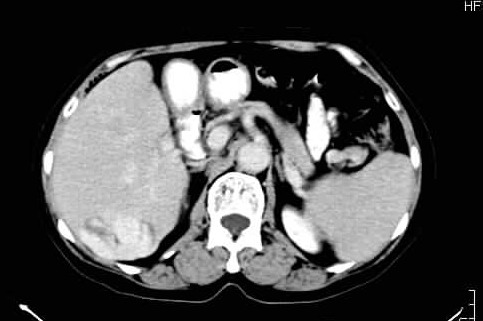

标题: CT24035:肝内占位

肝右叶后段低密度块影,增强后造影剂逐渐向病灶充填,支持肝血管瘤。

右叶后段血管瘤,层面少,看不见左叶,脾大。

肝右叶后段血管瘤、肝左叶缺如、脾大